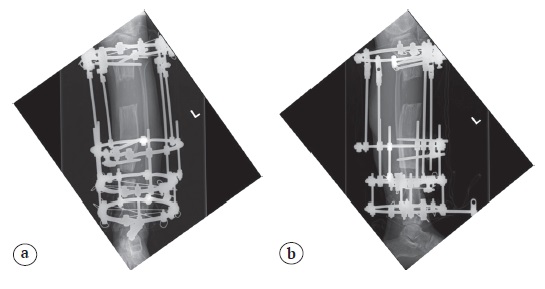

The strategies of treatment were to resect the osteomyelitis focus and perform a new proximal metaphyseal tibial osteotomy for antegrade bifocal bone transport with the Ilizarov technique (Figure 5). During the lengthening process, the patient experienced increasing pain, the flexion was limited to 120°. X-rays of the patella infera with the Caton-Deschamps ratio negative of 0.51 (normal = 1.3±0.6) were obtained (Figure 6).

Figure 5. AP (a) and lateral X-rays (b) at the beginning of bone transport. Note the patella height continues to get worse (b)

Figure 6. AP (a) and lateral X-rays (b) close to the end of bone transport when lowering of the patella was clinically evident (the Caton-Deschamps ratio negative)